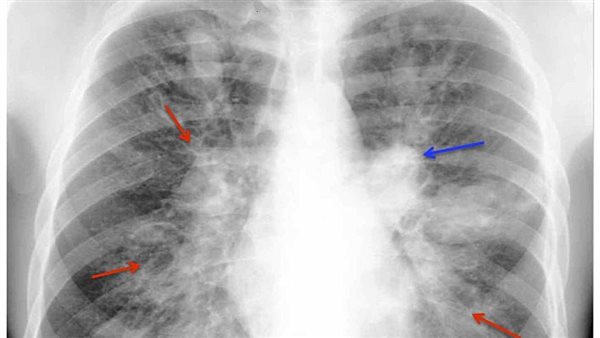

- اختبارات التصوير، مثل الأشعة السينية والتصوير المقطعي المحوسب، والتي تستخدم للكشف عن الكتل الفطرية أو العلامات المميزة للعدوى الغازية.